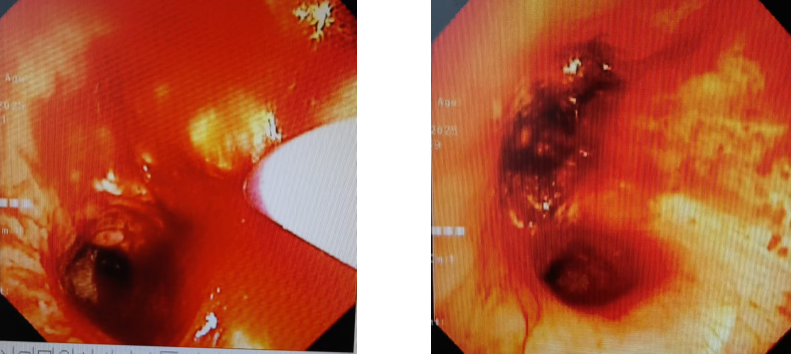

2.肿瘤切除:将可电圈套器圈住肿瘤进行切割;

3.即时显效:术后右中间支气管通畅,右中叶及下叶支气管畅通。

术后效果:患者胸闷、气促症状显著缓解。